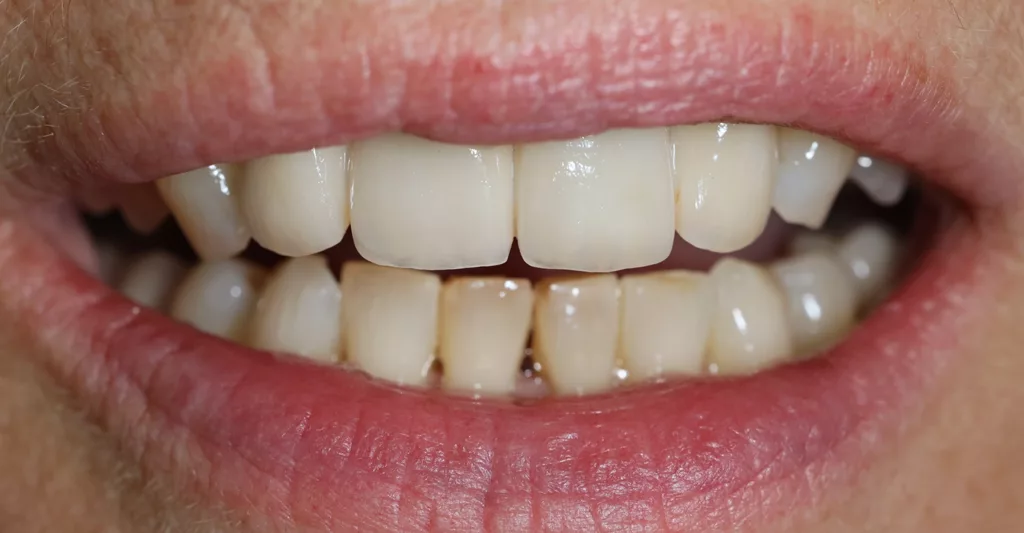

Die 38-jährige Patientin war optisch nicht zufrieden mit ihren Kronen an 11 und 21. Sie entschied sich ebenfalls für eine vollkeramische Neuversorgung. Nach Abnahme der Kronen zeigten sich die Zahnstümpfe moderat verfärbt, weshalb in diesem Fall die Zirkoniumdioxidgerüste CAD/CAM-gestützt aus VITA YZ HT A3 gefertigt wurden, um die bestimmte Grundzahnfarbe schon von innen heraus zu unterstützen (Abb. 10). Die Verblendung erfolgte hier mit der Feinstruktur-Feldspatkeramik VITA VM 9 für Zirkoniumdioxid.